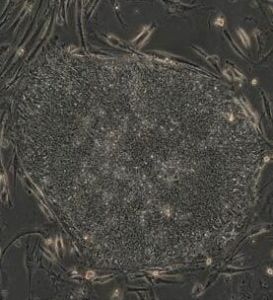

成熟細胞再編程技術科研人員以老鼠細胞為對象,通過植入僅僅4個基因,成功培育出“誘導式多能幹細胞”。2008年,科學家們在這一領域繼續前進,成果豐碩。

有兩個科研小組從罹患不同疾病的患者身上提取細胞,重新編程,使其“變身”為幹細胞。他們選取的疾病大多數很難或者不可能用動物模型來進行研究,這就使得獲取人類細胞系進行研究的需求變得更為迫切。這些被改造的細胞能夠在實驗室中生長並分裂,這一點與大多數成體細胞不同,因為成體細胞一般不能在培養的情況下存活。改造後的這些細胞接著被“誘導”,分化出全新特性的細胞類型,其中就包括那些受頑疾影響最大的細胞。

細胞基因重組工程的里程碑,可從2006年前談起。當年研究員進行老鼠實驗,透過添加4條基因,成功抹去細胞的發展記憶,當細胞“時光倒流”至原始胚胎狀態,科學家便可誘導培育成另一類細胞。

科學家在此基礎上取得3大突破。2008年7月份,波士頓哈佛幹細胞學院一支研究小組,從一名患上運動神經元疾病的82歲女病人抽取細胞,轉化成幹細胞,再培育成脊椎神經細胞。研究員透過在實驗室觀察神經生長,目睹疾病生成與發展過程,這是無法通過觀察病人取得的研究成果。

另一支研究團隊利用10種疾病的病人細胞,培育出幹細胞,這些病人罹患的疾病包括肌肉萎縮、一型糖尿病和唐氏綜合症等。研究員取得成功後,正研究如何加強技術的效率和安全性。

第3支研究團隊另闢蹊徑,跳過幹細胞的階段,直接將成熟老鼠的胰臟外分泌細胞,轉化成負責製造胰島素的beta細胞。以上3項研究所製造的新細胞株,有助認識疾病發展和研究治療藥方,當科學家能更精細、有效和安全地掌握細胞工程技術,便可利用病人的自身細胞治病,甚至培育器官。